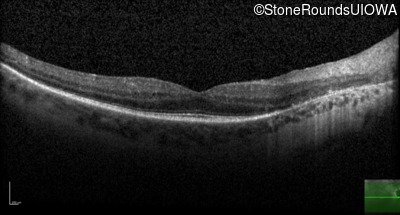

OCT Stack

20/32

20/32 -1

20/30 -2

20/32 -2

20/40

20/25 sc